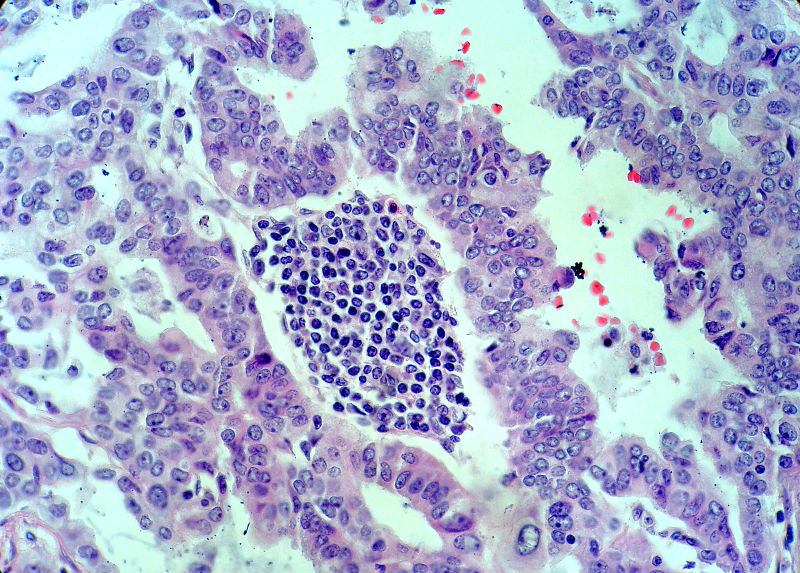

男,82岁,小肠穿孔紧急手术。

大体,小肠一段,长约60厘米,与粘膜面可见三个溃疡型肿物,肠系膜淋巴结肿大。

肿瘤呈巢片状分布,细胞大小相对一致,胞浆丰富,胞核呈细颗粒状,可见小核仁,血管较丰富,考虑神经内分泌肿瘤,加做免疫组化(Ki67、Syn、NSE、CgA、CD56)分级。

腺癌,部分为神经内分泌癌

神经内分泌癌。